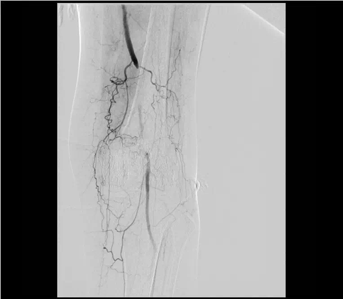

股動(dòng)脈閉塞